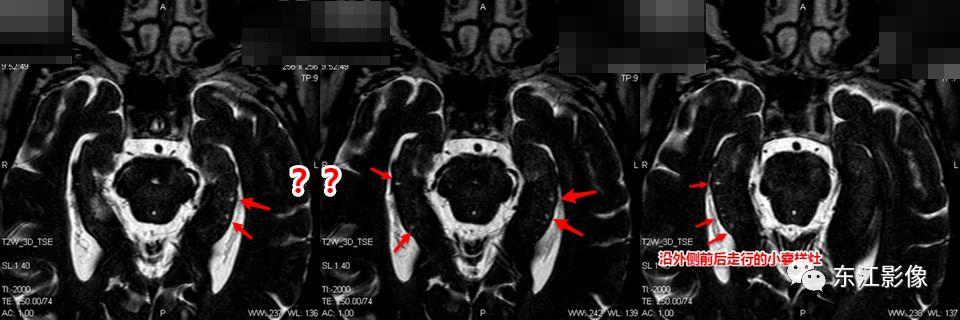

4. 海马沟残余囊肿

- 海马沟残余囊肿是常见的正常变异,影像学表现为串状分布的小的脑脊液样“囊肿”,位于海马区域,紧邻侧脑室颞角内侧。

- 一般是由于胚胎期海马角和齿状回的缺陷或不完全融合所致,不引起临床症状。

- 由于MRI的广泛应用,检出率非常高,尤其是薄层图像。

- 不熟悉的话,容易被误认为腔隙灶或囊肿。

海马沟残余囊肿。

又一例。

另一例,薄层显示更佳。